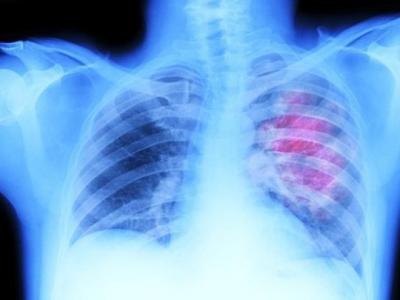

英国最新研究发现接受胸腔放射治疗 末期

(神秘的地球报道)英国最新研究发现,患上末期小细胞肺癌(SCLC)的患者,若接受胸腔...